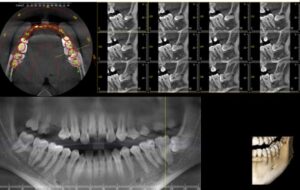

TOMOGRAFIA AXIAL COMPUTADA POR TECNOLOGÍA CONE BEAM

RADIOGRAFIA PANORAMICA

TAC DENTAL DENTA SCAN

ESTUDIOS PRE-IMPLANTOLOGICOS